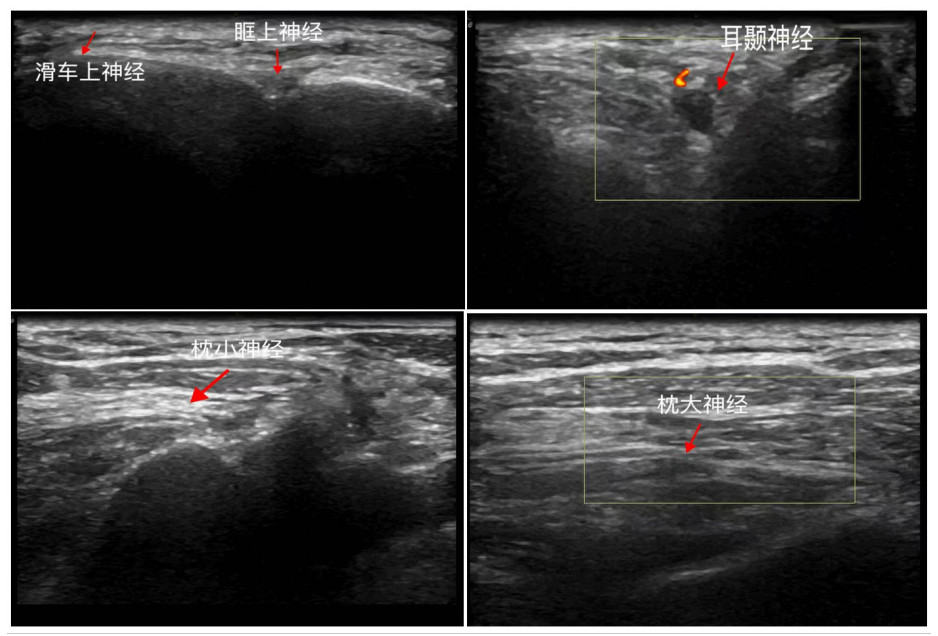

干预措施:两组患者静脉输注负荷剂量右美托咪定(批号:12407291,遂成药业股份有限公司)1 μg/kg 10 min,后以0.3 μg/(kg·h)的速率持续泵注。SD组在气管插管机械通气完成后,行手术侧超声引导SNB,给予0.6%的甲磺酸罗哌卡因注射液(批号:24112951,石家庄四药有限公司),分别行眶上(2 mL)、滑车上(2 mL)、耳颞(2 mL)、枕大(5 mL)和枕小(5 mL)神经阻滞(图 1)。所有操作由两名熟练掌握超声引导SNB的高年资麻醉医师完成。

| 图 1 超声引导SNB Fig 1 Ultrasound-guided SNB |